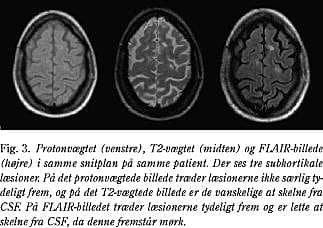

Akutte og kroniske MS-læsioner er hyperintense på T2-vægtede og protonvægtede billeder (Fig. 1). Det samme er tilfældet for de fleste andre patologiske forandringer som for eksempel inflammatoriske, infektiøse eller neoplastiske forandringer. Hyperintensiteten skyldes blandt andet øget vandindhold, hvilket ses ved både ødem, demyelinisering, remyelinisering, gliose og axontab.

Den enkelte MS-læsion er relativt velafgrænset og oftest rund eller ovoid og varierer fra få mm til mere end 1 cm i størrelse. Læsionerne kan konfluere - især periventrikulært - hvilket kan give et mere uregelmæssigt udseende (4).

I den akutte fase er læsionerne ofte mere diffust afgrænsede på grund af ødem. Herefter vil læsionerne oftest aftage i størrelse og intensitet. I sjældne tilfælde forsvinder de helt.